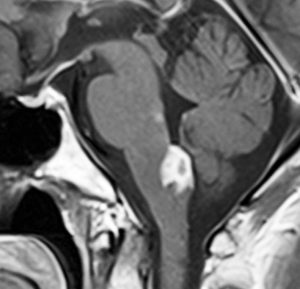

尿崩症にて発症した2年後にようやく小さなneurohypophyseal germinomaを発見された9歳女児例です。術前のT1強調画像では下垂体後葉のbrightnessが消失し,下垂体柄が腫大しています(左側)。ガドリニウムで腫瘍部分が増強されますが前葉よりは低信号となっています(右側)。経蝶形骨洞生検術で確定診断を得た後に,シスプラチンとエトポシドを1コース投与したところ腫瘍は完全消失しました。3コース後に24Gy12分割の放射線治療を加え再発はありません。残っていた下垂体前葉機能は治療後に少し改善しました。生検術では,トルコ鞍底を開けて下垂体後葉の下部を目標にして小さな組織採取をします。GHDがあっても前葉にはmassとしての腫瘍が無いと考えた方がいいでしょう。

この例は18歳,HCG 0.1mIU/ml,尿崩症で発症しました。神経下垂体ジャーミノーマなので,下垂体前葉のみが残って後葉から視床下部が腫瘍化しています。よくよく見ると松果体にもごく小さな腫瘍があります。右のCISS画像で松果体の腫瘍化が明瞭です。

経鼻生検術で下垂体後葉部分がgerminomaということを確認してからICE (IFO/CDDP/VP-16)を1コース加えて3週間後の画像です。腫瘍は灰白隆起の部分を残してほぼ消失しています。松果体部の腫瘍も消えています。典型的なgerminomaの化学療法反応性を示しています。下垂体前葉機能は正常,尿崩症も少し良くなりました。